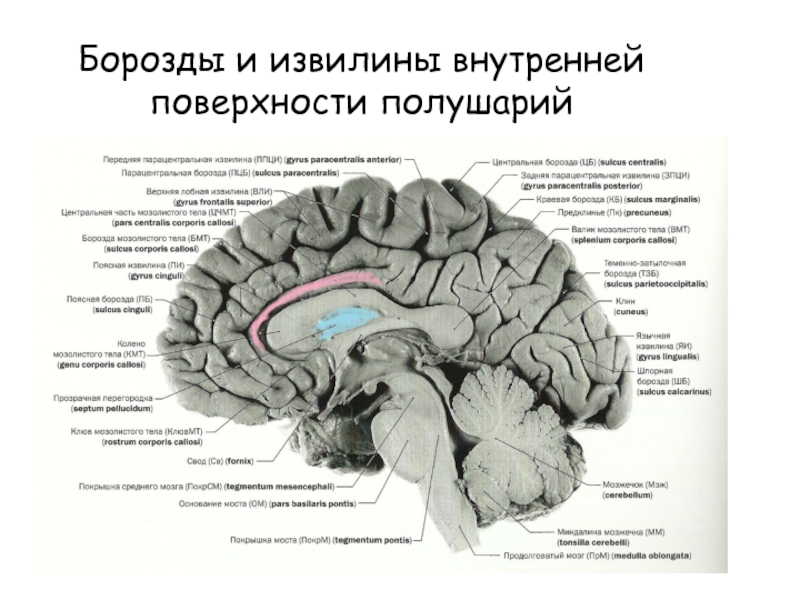

Анатомические снимки верхнелатеральной поверхности головного мозга